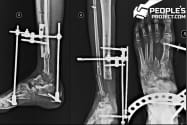

Один із тяжкопоранених бійців через два роки страждань нарешті став на ноги

Поранений боєць став на ноги Фото: The People\'s Project

Травми Віталій отримав ще в січні 2015 року, в жорстоких боях за Донецький аеропорт. На злітній смузі, просто за кілька метрів від чоловіка, жахнула мінометна міна.

Військовий пережив усе - гнійно-некротичні процеси, незрощення, остеомієліти, численні пластики з ре позиціонуванням, місяці в апаратах Ілізарова та зовнішньої фіксації. За два роки лікування, він таки став на власні ноги.